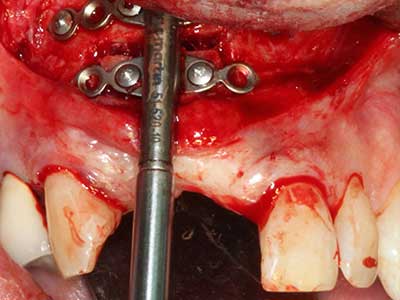

When surgical procedures are performed on bone in the immediate vicinity of sensitive structures such as blood vessels or nerves, rotary instruments pose a significant risk of iatrogenic injury. Piezoelectric devices can be helpful for preparation of bone covers and removal of hard tissue close to nerves, particularly for exposure of nerves after iatrogenic injury but also during nerve lateralization for resective and reconstructive procedures or implant placement (Fig. 17-20). Light contact between the piezotip and the nerve does not generally result in damage but proceeding incautiously with saw-like motions or attachments where a residual bone substrate remains may cause temporary or even permanent nerve damage. However, the risk of damage is considered to be substantially lower than when using saws or milling instruments (Pereira, Gealh et al. 2014).